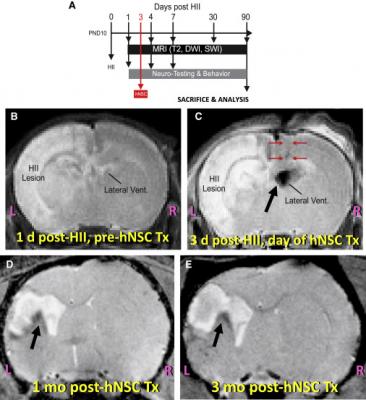

Experimental Protocol and Representative MRI of Brains at Various Key Points in That Protocol. (A) Experimental timeline. (B) Representative T2WI (using an 11.7T MRI) of the brain of a postnatal day (PND) 11 pup, 1 day after inducing left HII and prior to hNSC transplantation. Note the beginning of an increasingly intense “water signal” (white) on the left (“HII lesion”). (C) Representative T2WI (using an 11.7T MRI) 3 days post-HII, shortly after implantation of SPIO pre-labeled hNSCs into the contralateral cerebral ventricle (“Lateral Vent”). Note the “HII lesion” on the left becoming hyperintense (white) and the black signal void of the SPIO-labeled hNSCs in the lateral ventricle (black arrow). Red arrows denote the needle track. In contrast to what occurs in the intact brain (Figure S4), in a brain subjected to left HII, the implanted SPIO-labeled hNSCs (black signal void) (black arrow) migrate from the right (“R”) to the left (“L”) hemisphere to enter the lesion. (D and E) Shown here (using a 4.7T MRI) are SPIO-labeled hNSCs (black signal void) (black arrow) at 1 month post-implantation into the contralateral ventricle (D) and, in the same representative animal, at 3 months post-implantation (E)–stably integrated and surrounding a much-reduced residual lesion, with no interval enlargement of the graft or ventricles.